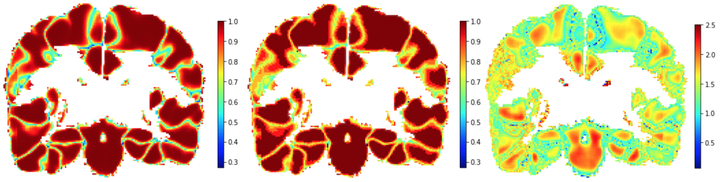

Deep segmentation networks typically create their outputs via a softmax. Hence, the assignment appears to be probabilistic. However, it has been shown in literatute that interpreting these softmax outputs as label probabilities is not reliable and that they tend to be overly confident. A simple approach to counteract this phenomenon for classification problems is to use Temperature Scaling which rescales the inputs to the softmax via a global temperatute constant so that the resulting outputs are consistent with the empirically observed labeling performance, i.e., the softmax output become calibrated probabilites. Our Local Temperature Scaling approach extends this principle to image segmentation. In particular, it allows for localized probability calibrations.